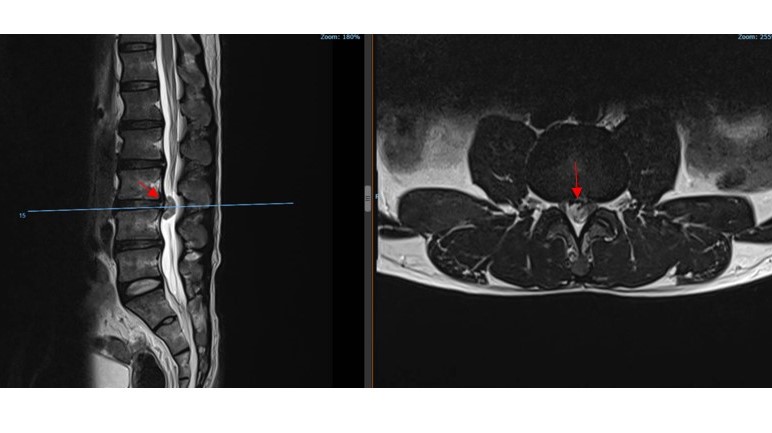

Thoát Vị Đĩa Đệm Cột Sống Thắt Lưng Trong Màng Cứng: Báo Cáo Trường Hợp Lâm Sàng Hiếm Gặp

BSNT Lê Trọng Hiếu, BSNT Nguyễn Hữu Hợp, BSNT Trần Đức Hoàng, BSNT Lê Nguyên Phước, BSNT Võ Nhật Quang, Ths.BSCKII Nguyễn Thanh Minh